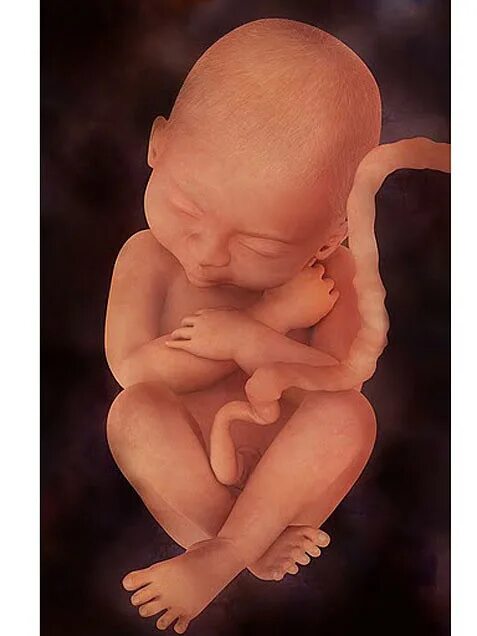

Сейчас 23 недели